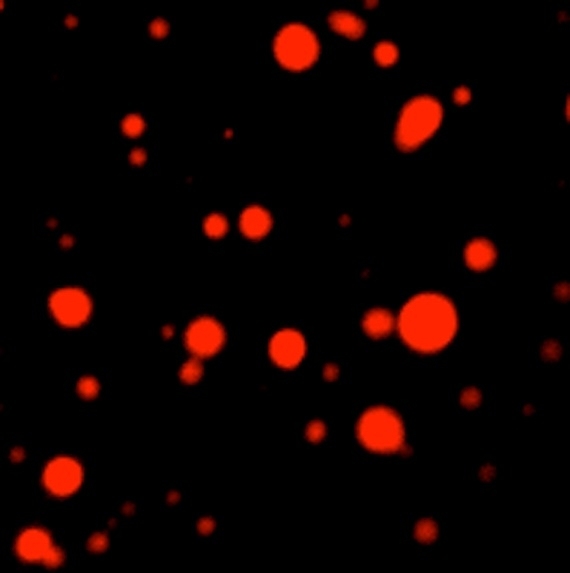

The researchers created their own suite of four different fluorescently-labeled condensates by adding glowing tags to marker proteins specific to each kind of droplet. For example, transcriptional condensates are marked by the droplet-forming protein MED1, splicing speckles by a protein called SRSF2, and nucleoli by FIB1 and NPM1.

The researchers added the cancer drugs to a mixture containing various droplets (and only droplets, none of the actual drug targets), and found that the drugs sorted themselves into specific condensates. Mitoxantrone concentrated in condensates marked by MED1, FIB1 and NPM1, selectively avoiding the others. Cisplatin, too, showed a particular affinity for droplets held together by MED1.